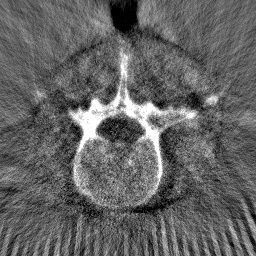

Disentanglement and explicit shape constraints. As shown in Fig. 4, we can see streak metal artifacts nearly everywhere in . M1 can roughly disentangle artifacts and anatomical information but strong vertical artifacts and strange air area appear in (see red arrows of M1 in Fig. 4). For the anatomical structure, M1 learns to segment vertebrae with fully supervised and applied on various CT images, but fails to suppress the false bony structure in and as may misclassify some metal artifacts as bone.

Implicit shape constraints. With , all segmentations are improved with higher Dices and smaller ASDs, see Table 1. As shown in Fig. 4, , and become similar but the high density bone is not correctly segmented in as it maybe treated as metal artifacts. Comparing between M2 and M1, the abnormal air region disappears but metal artifact reduction performance is still not satisfactory.

Anatomy-aware generation. With AADE layer in M3, , and are substantially improved as shown in Table 1. Note, is used as attention map, so we do not expect it to be identical to . In , metal artifacts are further suppressed comparing with M2. Thus, AADE is critical to our anatomy-aware artifact disentanglement framework. With the special structure, can be punished in the image translation and reconstruction processes and the other encoders and generators receive more guidance. However, as shown by blue arrows in Fig. 4, we observe a shadow of vertebra edge of appears in of M3 and the vertebra boundaries get smoothed out in . It may be because sharp edges are encoded as metal artifacts and forced to be added to by artifact consistency loss .

Removal of . To mitigate vertebrae shadows, we remove . The segmentation performance of most images in M4 gets improved because of better synthetic images. Overall, in M4 yields the best segmentation performance for CBCT images with an average Dice of 0.847 and an average ASD of 1.54 mm. For the synthetic images, M4 generates with the best quality and least metal artifacts among all the models. M4 also outputs without vertebra shadows. The results indicate our shape-aware network could preserve anatomical details and transfer the metal artifacts precisely without .